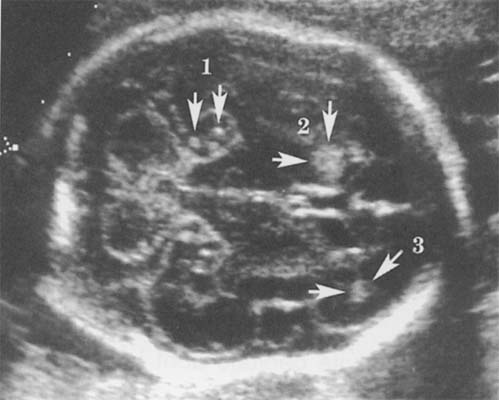

Séméiologie échographique :

Les données post natales montrent que seulement 10 à 20 % des enfants sont symptomatiques et sont donc susceptibles de développer des anomalies décelables in utero. Il est cependant probable que seuls les fœtus présentant les atteintes les plus sévères présenteront des signes échographiques. L'échographie ne montrerait en pratique des signes d'infection que chez 5% des enfants atteints (93).

La séméiologie échographique décrite par les différents auteurs comporte les signes suivants :